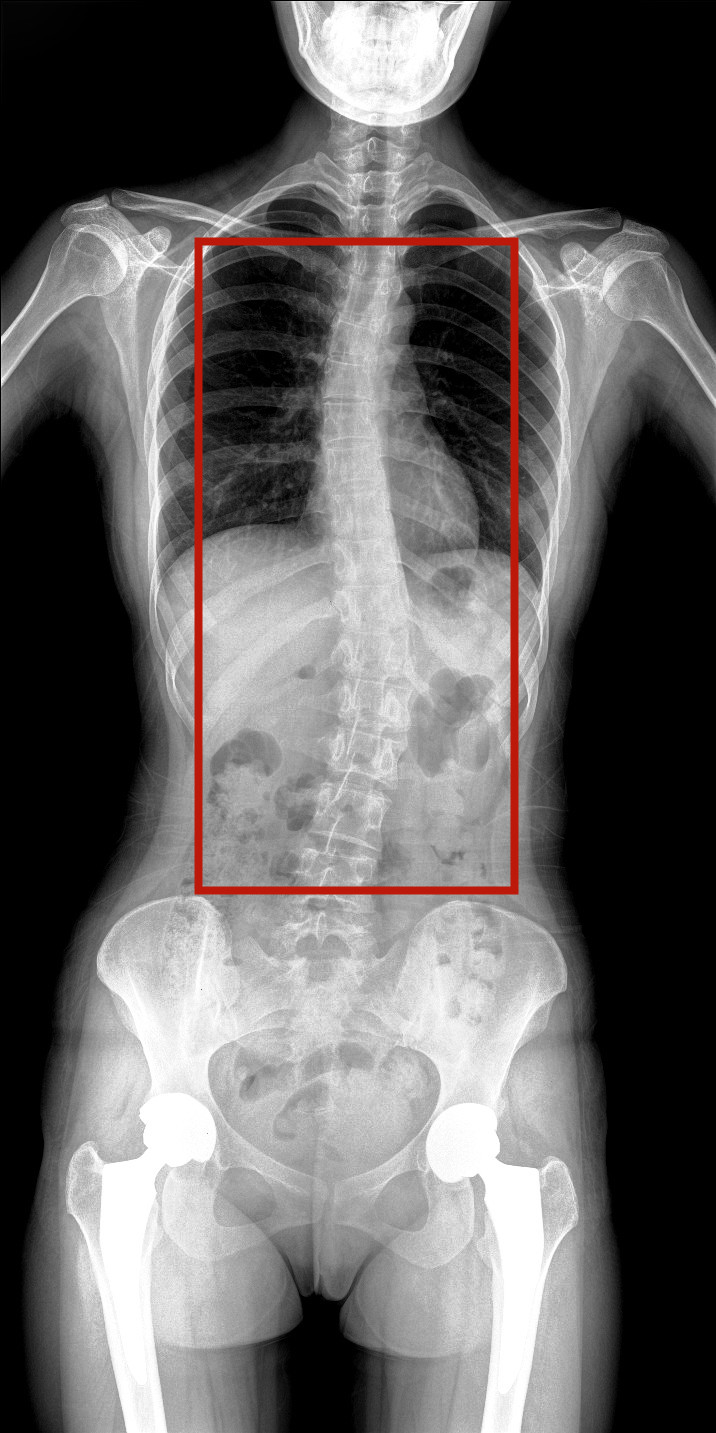

病情描述:患者,女,23歲,免疫系統(tǒng)畸變導(dǎo)致的脊柱側(cè)彎

虛線框示患者脊柱側(cè)彎明顯

脊柱圖像范圍包含脊椎、雙側(cè)肩部及骨盆。片內(nèi)頸椎、胸椎、腰椎、骶椎、雙肩及骨盆重組影像結(jié)構(gòu)清晰,對比度高,對位、對線好,接緣區(qū)無重疊、遺漏、縫隙。能夠滿足臨床測量脊柱Cobb角及臨床人體平衡線等指標的測量,整體上能對全脊柱進行觀察診斷。